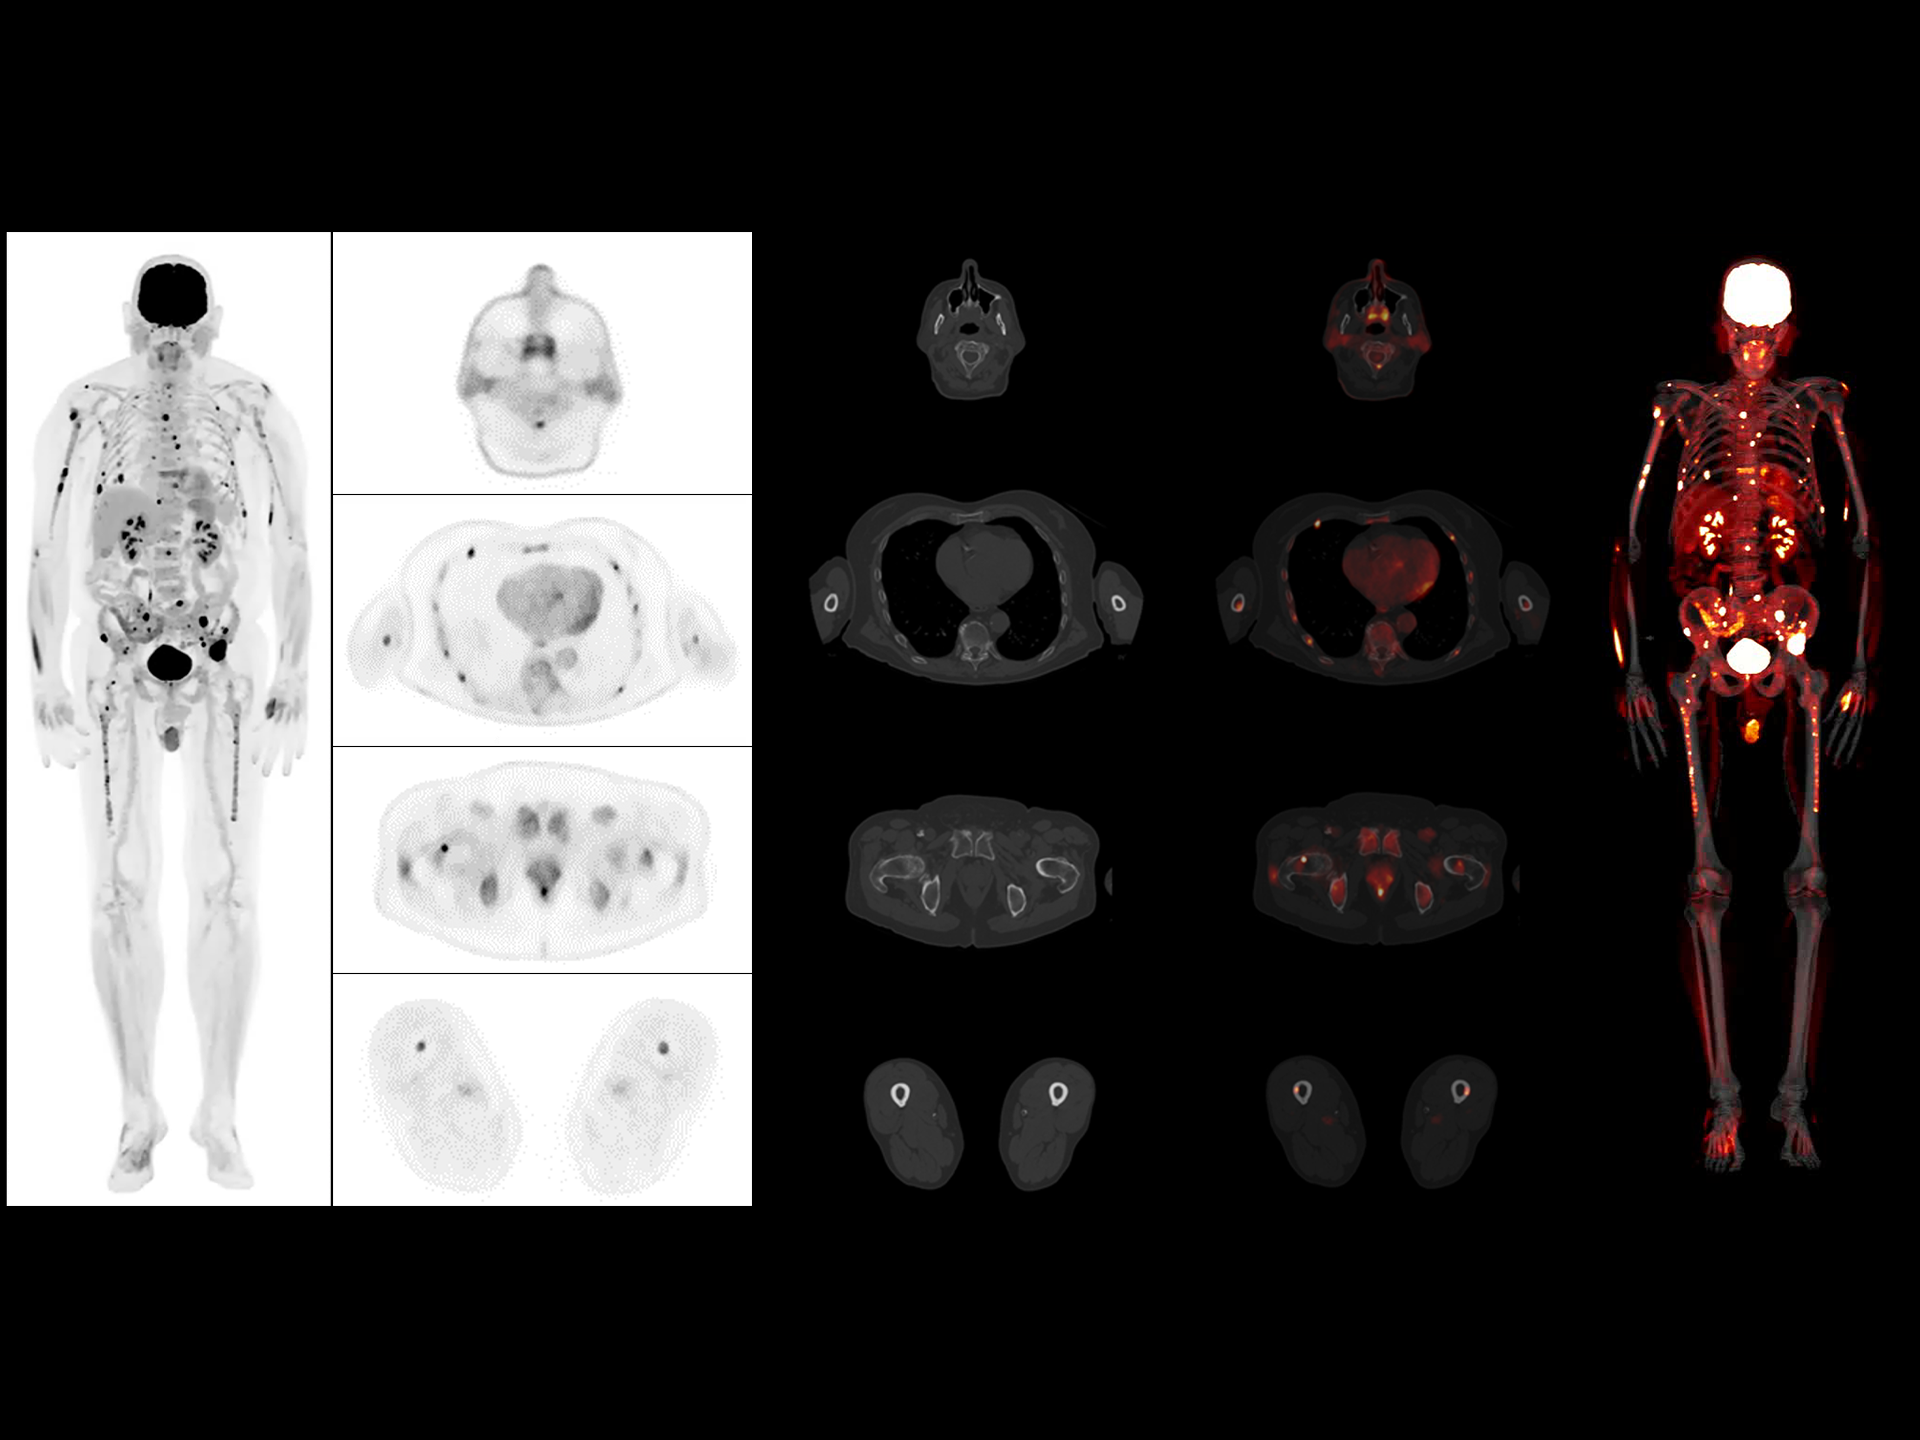

Scalable axial field of view that can be on-site upgraded for enhanced imaging capability and more clinical possibilities.